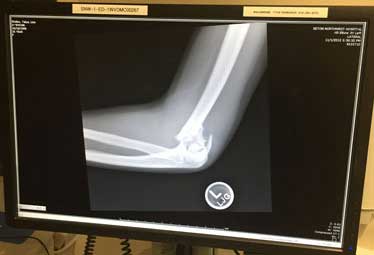

Using the secure EMR system, Dr. Padalecki looked at the X-ray from "wherever he was" on that Sunday night. He recommended ARC's hand specialist, Dr. Reichel for the surgery.

"I was in a state of blankness because I couldn't believe what was going on. And then, next thing I know Dr. Reichel came into the room," Talya recalls. "He pulled up the X-ray on the computer right next to me."

Dr. Reichel showed Talya where her elbow was broken and explained how he would repair it. "He made me 100% feel like I was going to be healed," Talya remembers